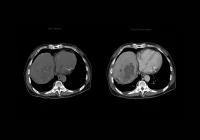

Radiomics enables the extraction of high-dimensional features from medical images, capturing patterns that may not be visually discernible. This study used T2W FLAIR images from a large multicentre cohort comprising 1727 participants, including both PD patients and HCs, to extract radiomics features from four brain regions known to be implicated in PD: the substantia nigra (SN), red nucleus (RN), globus pallidus (GP) and putamen (PU). After manual segmentation and validation of these regions of interest, a total of 7124 features were extracted and refined using dimension reduction techniques such as LASSO and mRMR, ultimately selecting 20 highly diagnostic features.

These features included five from SN, two from RN, three from GP and ten from PU. All were higher-order texture features, suggesting that PD-related changes are too subtle to detect using basic intensity or shape-based analyses. The SN-derived features showed the highest diagnostic importance, reflecting the critical role of dopaminergic neuron degeneration in PD. PU features also contributed significantly, aligning with known patterns of dopaminergic loss and structural changes in the striatum during disease progression. Together, these features formed the basis for model training and testing using six ML algorithms.